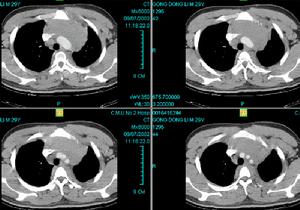

侵蝕性葡萄胎2.轉移灶表現症狀、體徵視轉移部位而異。最常見部位是肺,其次是陰道、宮旁,腦轉移少見。在肺轉移早期,胸片顯示肺野外帶單個或多個半透明小圓形陰影為其特點,晚期病例所見與絨癌相似。陰道轉移灶表現為紫藍色結節,潰破後大量出血。腦轉移典型病例出現頭痛、嘔吐、抽搐、偏癱及昏迷,一旦發生,致死率高。

3、線胸片:可見肺棉球樣轉移灶。